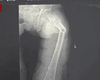

01.06.2024 22:23 СвітФан 35-річний чоловік зламав найміцнішу кістку в тілі під час кашлю: відома причина